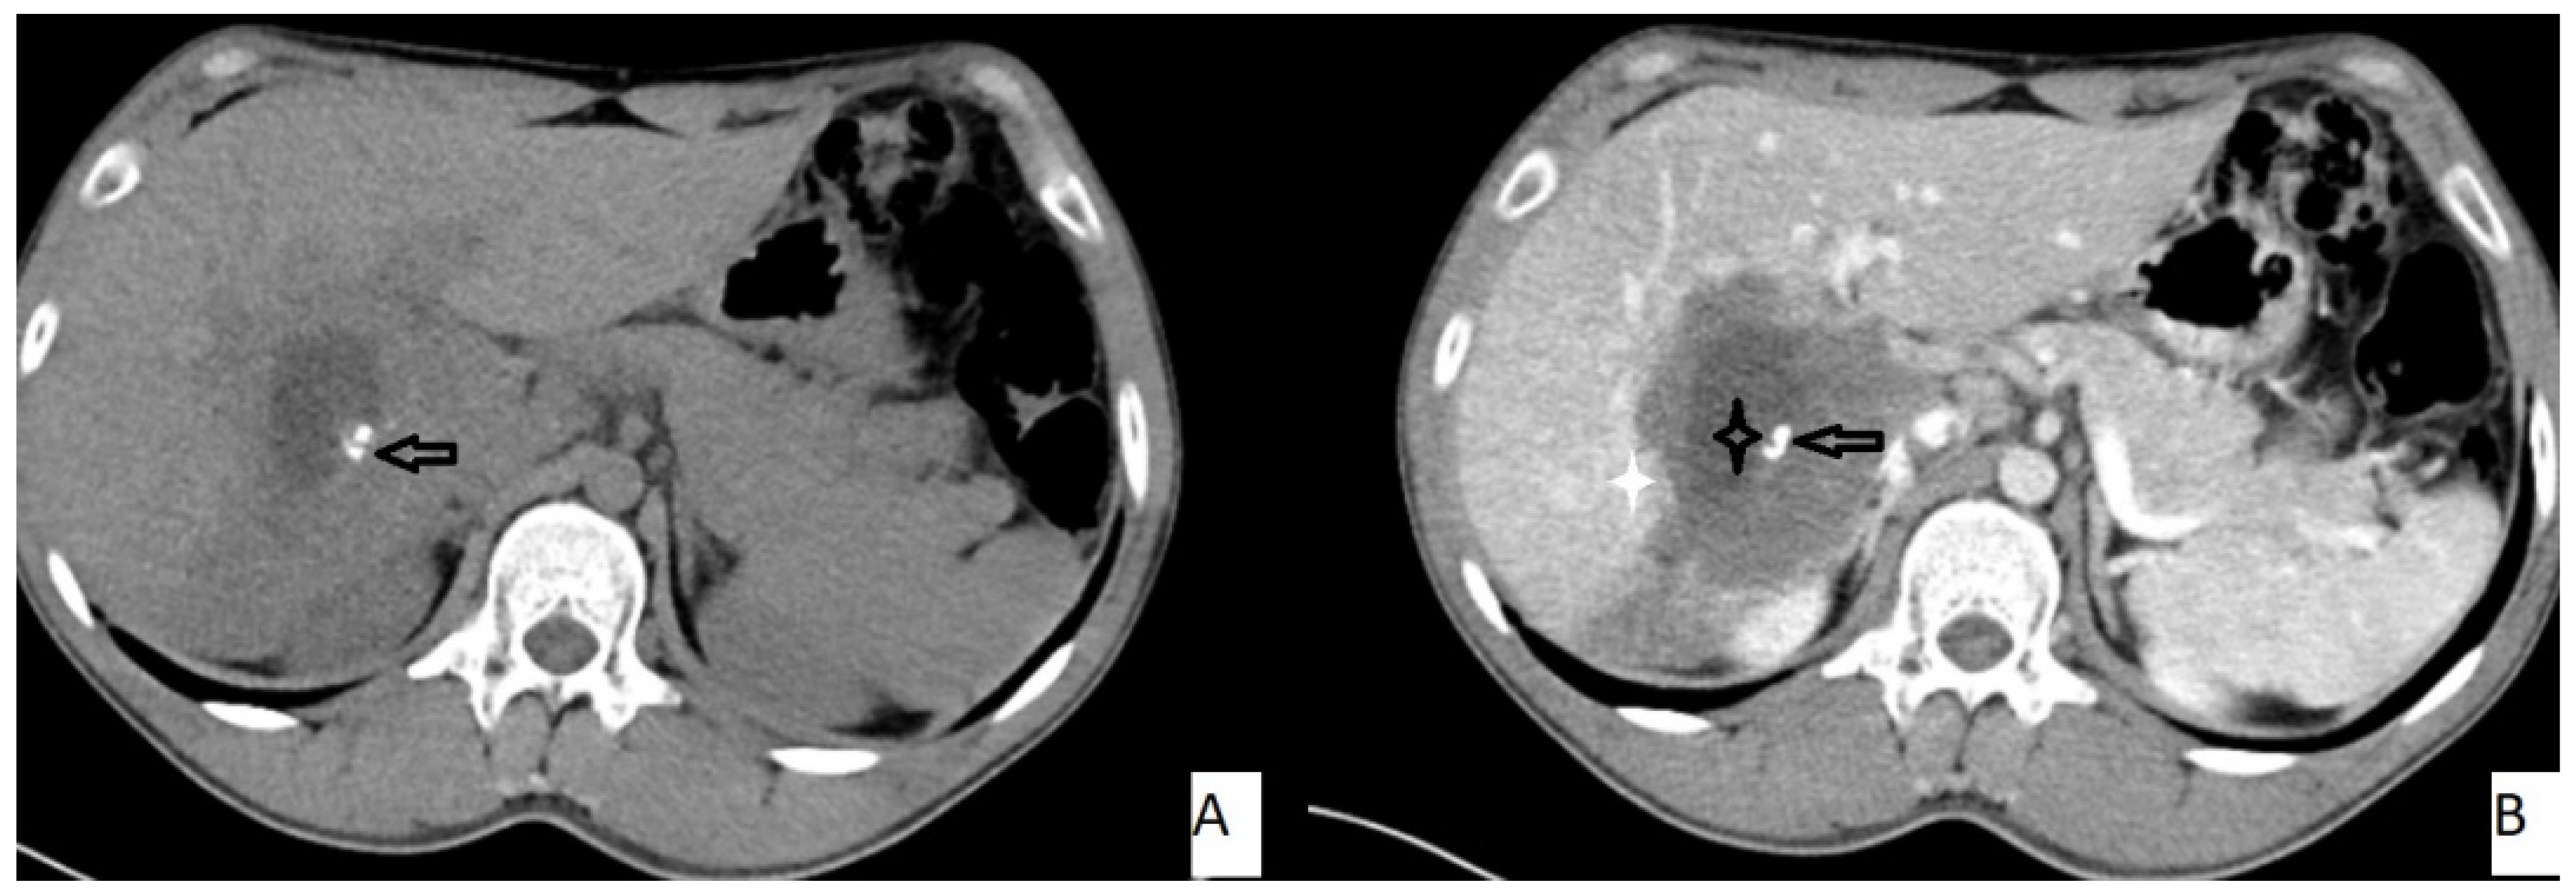

The most frequently encountered CT pattern was a heterogeneous mass with calcifications and hypoattenuating areas (72.3%). Most of the lesions had irregular contours (85.4%), 85.4% lacked contrast enhancement, 77.4% of the lesions had calcifications, and atrophy and capsular retraction was present in 10.7% of the lesions (Figure 2 and Figure 3). Table 3 details the distribution of CT appearances.

Figure 3.

53-year-old female. Hepatic lesion with irregular borders and calcification (A,B—arrows) on precontrast axial CT (A). On portal venous images (B), no enhancement is present in the lesion. Central necrosis can be seen (B—black star). Perilesional enhancement (B—white star) is present.